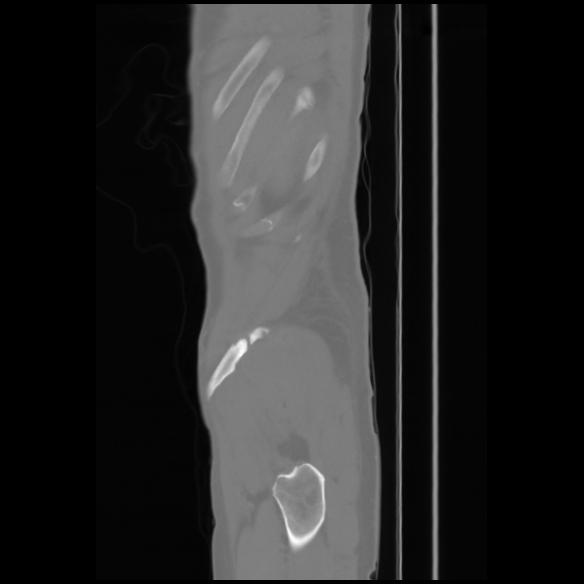

7 CUERPO,CE,Sagittal,3.000,CUERPO,Sagittal,